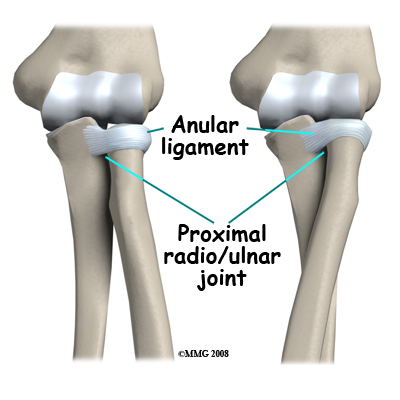

The joint between the radius and ulna is continuous with the joint between the humerus and the ulna/radius, meaning they are all encircled within the same joint capsule. There is a divot on the side of the ulna where the radial head rests and in which it rotates. The entire head of the radius is covered with articular cartilage. There is a ligament, the annular ligament that circles the radial head and keeps it snug against the ulna as it rotates. If the radial head or neck is fractured, due to the anatomy in this region the blood supply to the fractured fragments is at risk.